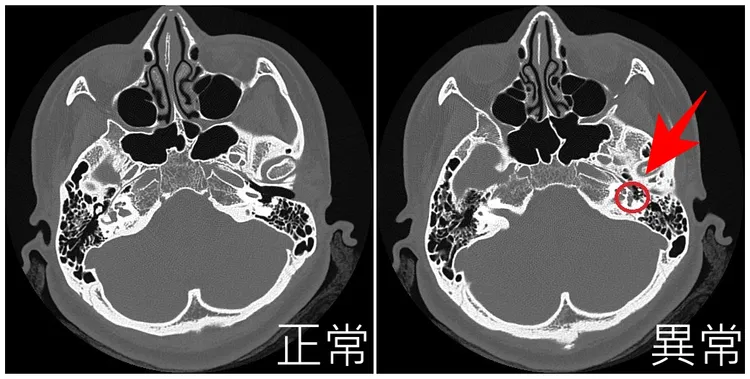

陳厚匡指出,患者到院後,先詢問其病史、聽力下降時間及相關家族史,並安排理學檢查與聽力檢查,確認是「傳導性聽力損失」而非「感音神經性聽力損失」,之後藉由CT斷層掃描,排除可能病因如中耳炎或中耳腫瘤後,果然在鐙骨底板發現中耳骨質病變,確認是「耳硬化症」惹的禍。

耳硬化症是因鐙骨骨質海綿化及硬化(圖右),導致出現傳導性聽力損失。亞大附醫提供